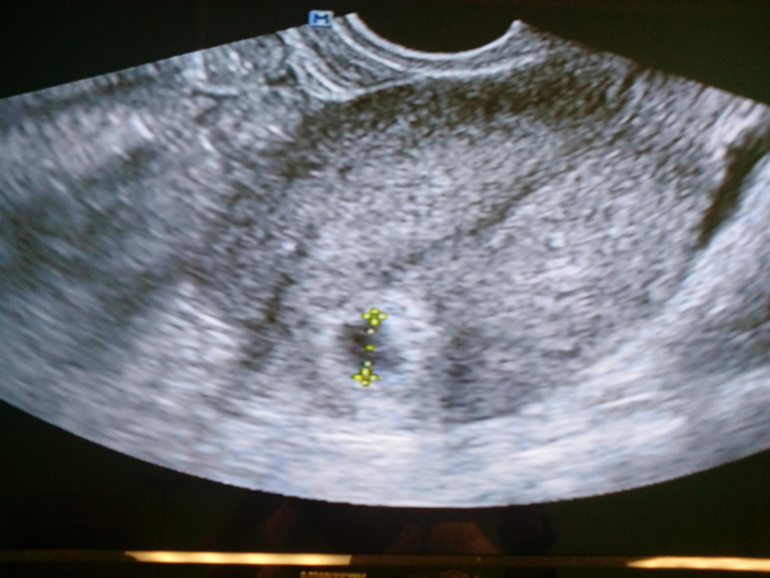

И вот сегодня наше первое УЗИ.

Пя в матке одно

Срок 5 акушерских недель и 5 дней